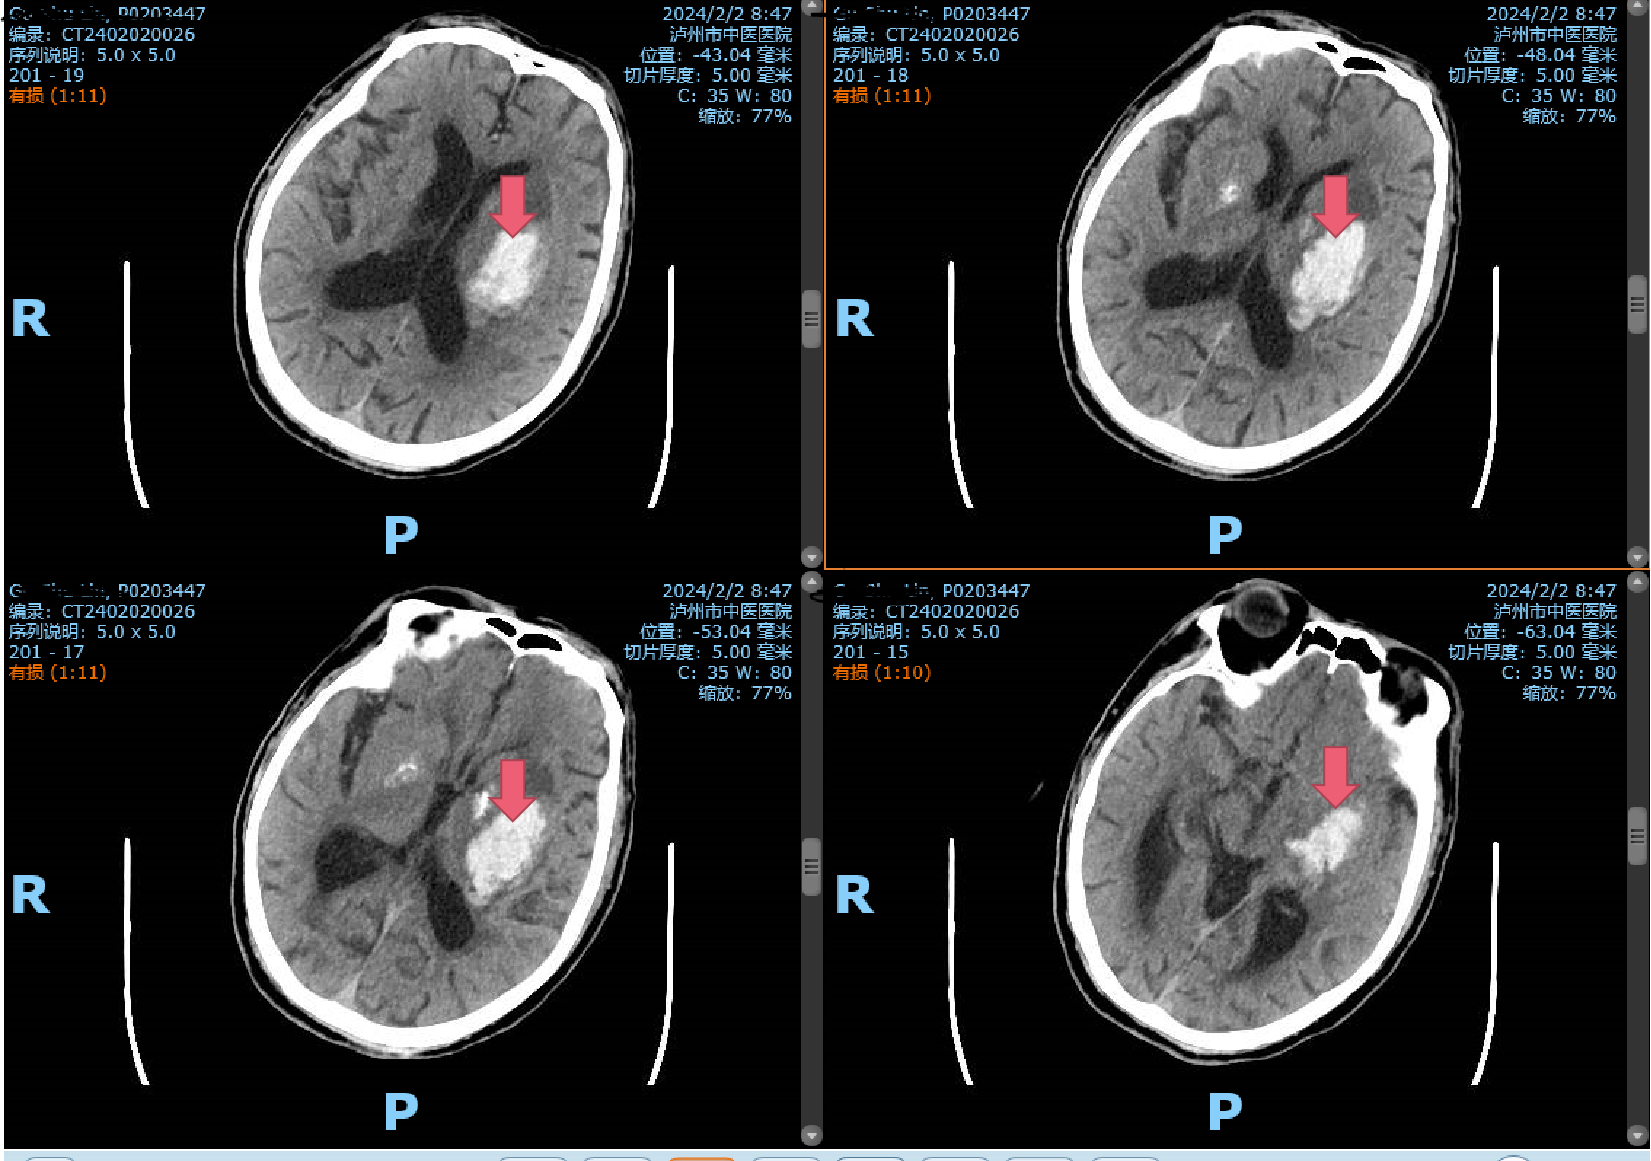

2月2日一早,一阵急促的响铃声打破了清晨的宁静,一位年逾古稀的辜先生在洗澡时突发一侧肢体无力,家属见状不知所措,焦急万分,情急之下将患者背下楼,直接送入泸州市中医医院急诊科!时间第一,生命至上。患者入院后直接经急救通道,完善头颅CT,提示脑出血,病情危重,立即及时、安全地送到了市中医院重症监护室,并...